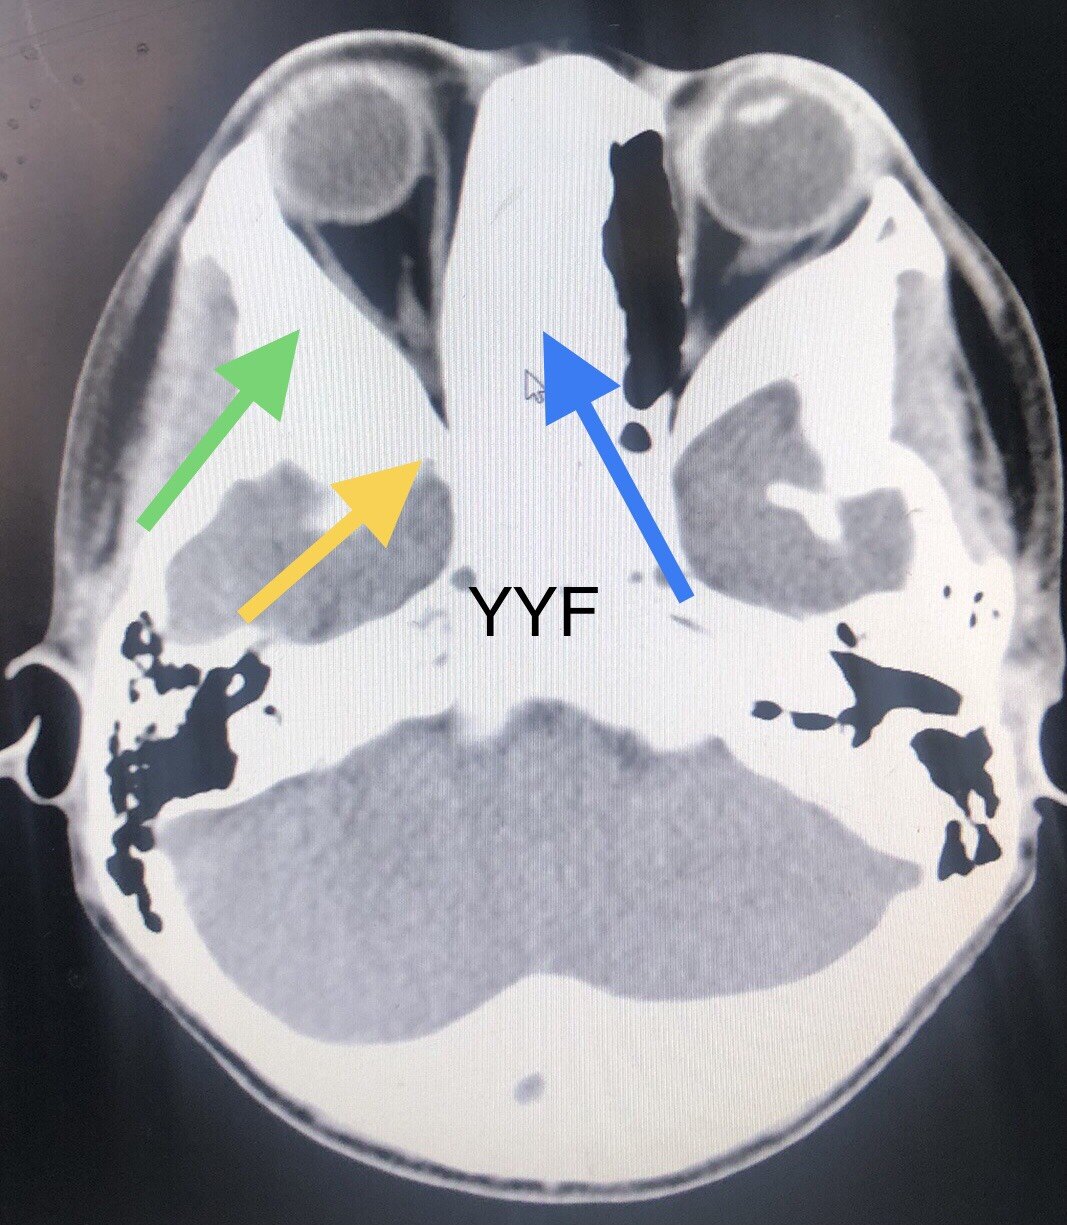

对多数此病来说,因为疾病不能根治

进展相对缓慢

黄色箭头视神经管处,蓝色箭头鼻窦引流,绿色箭头增厚可导致眼球突出

严重骨纤病变的表现